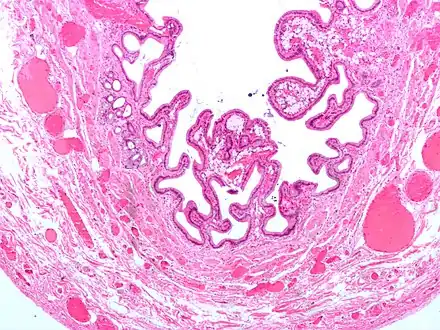

Micrograph of cholesterolosis of the gallbladder

Micrograph of cholesterolosis of the gallbladder Micrograph of cholesterolosis of the gallbladder

The name strawberry gallbladder comes from the typically stippled appearance of the mucosal surface on gross examination, which resembles a strawberry. Cholesterolosis results from abnormal deposits of cholesterol esters in macrophages within the lamina propria (foam cells) and in mucosal epithelium. The gallbladder may be affected in a patchy localized form or in a diffuse form. The diffuse form macroscopically appears as a bright red mucosa with yellow mottling (due to lipid), hence the term strawberry gallbladder. It is not tied to cholelithiasis (gallstones) or cholecystitis (inflammation of the gallbladder).[2]